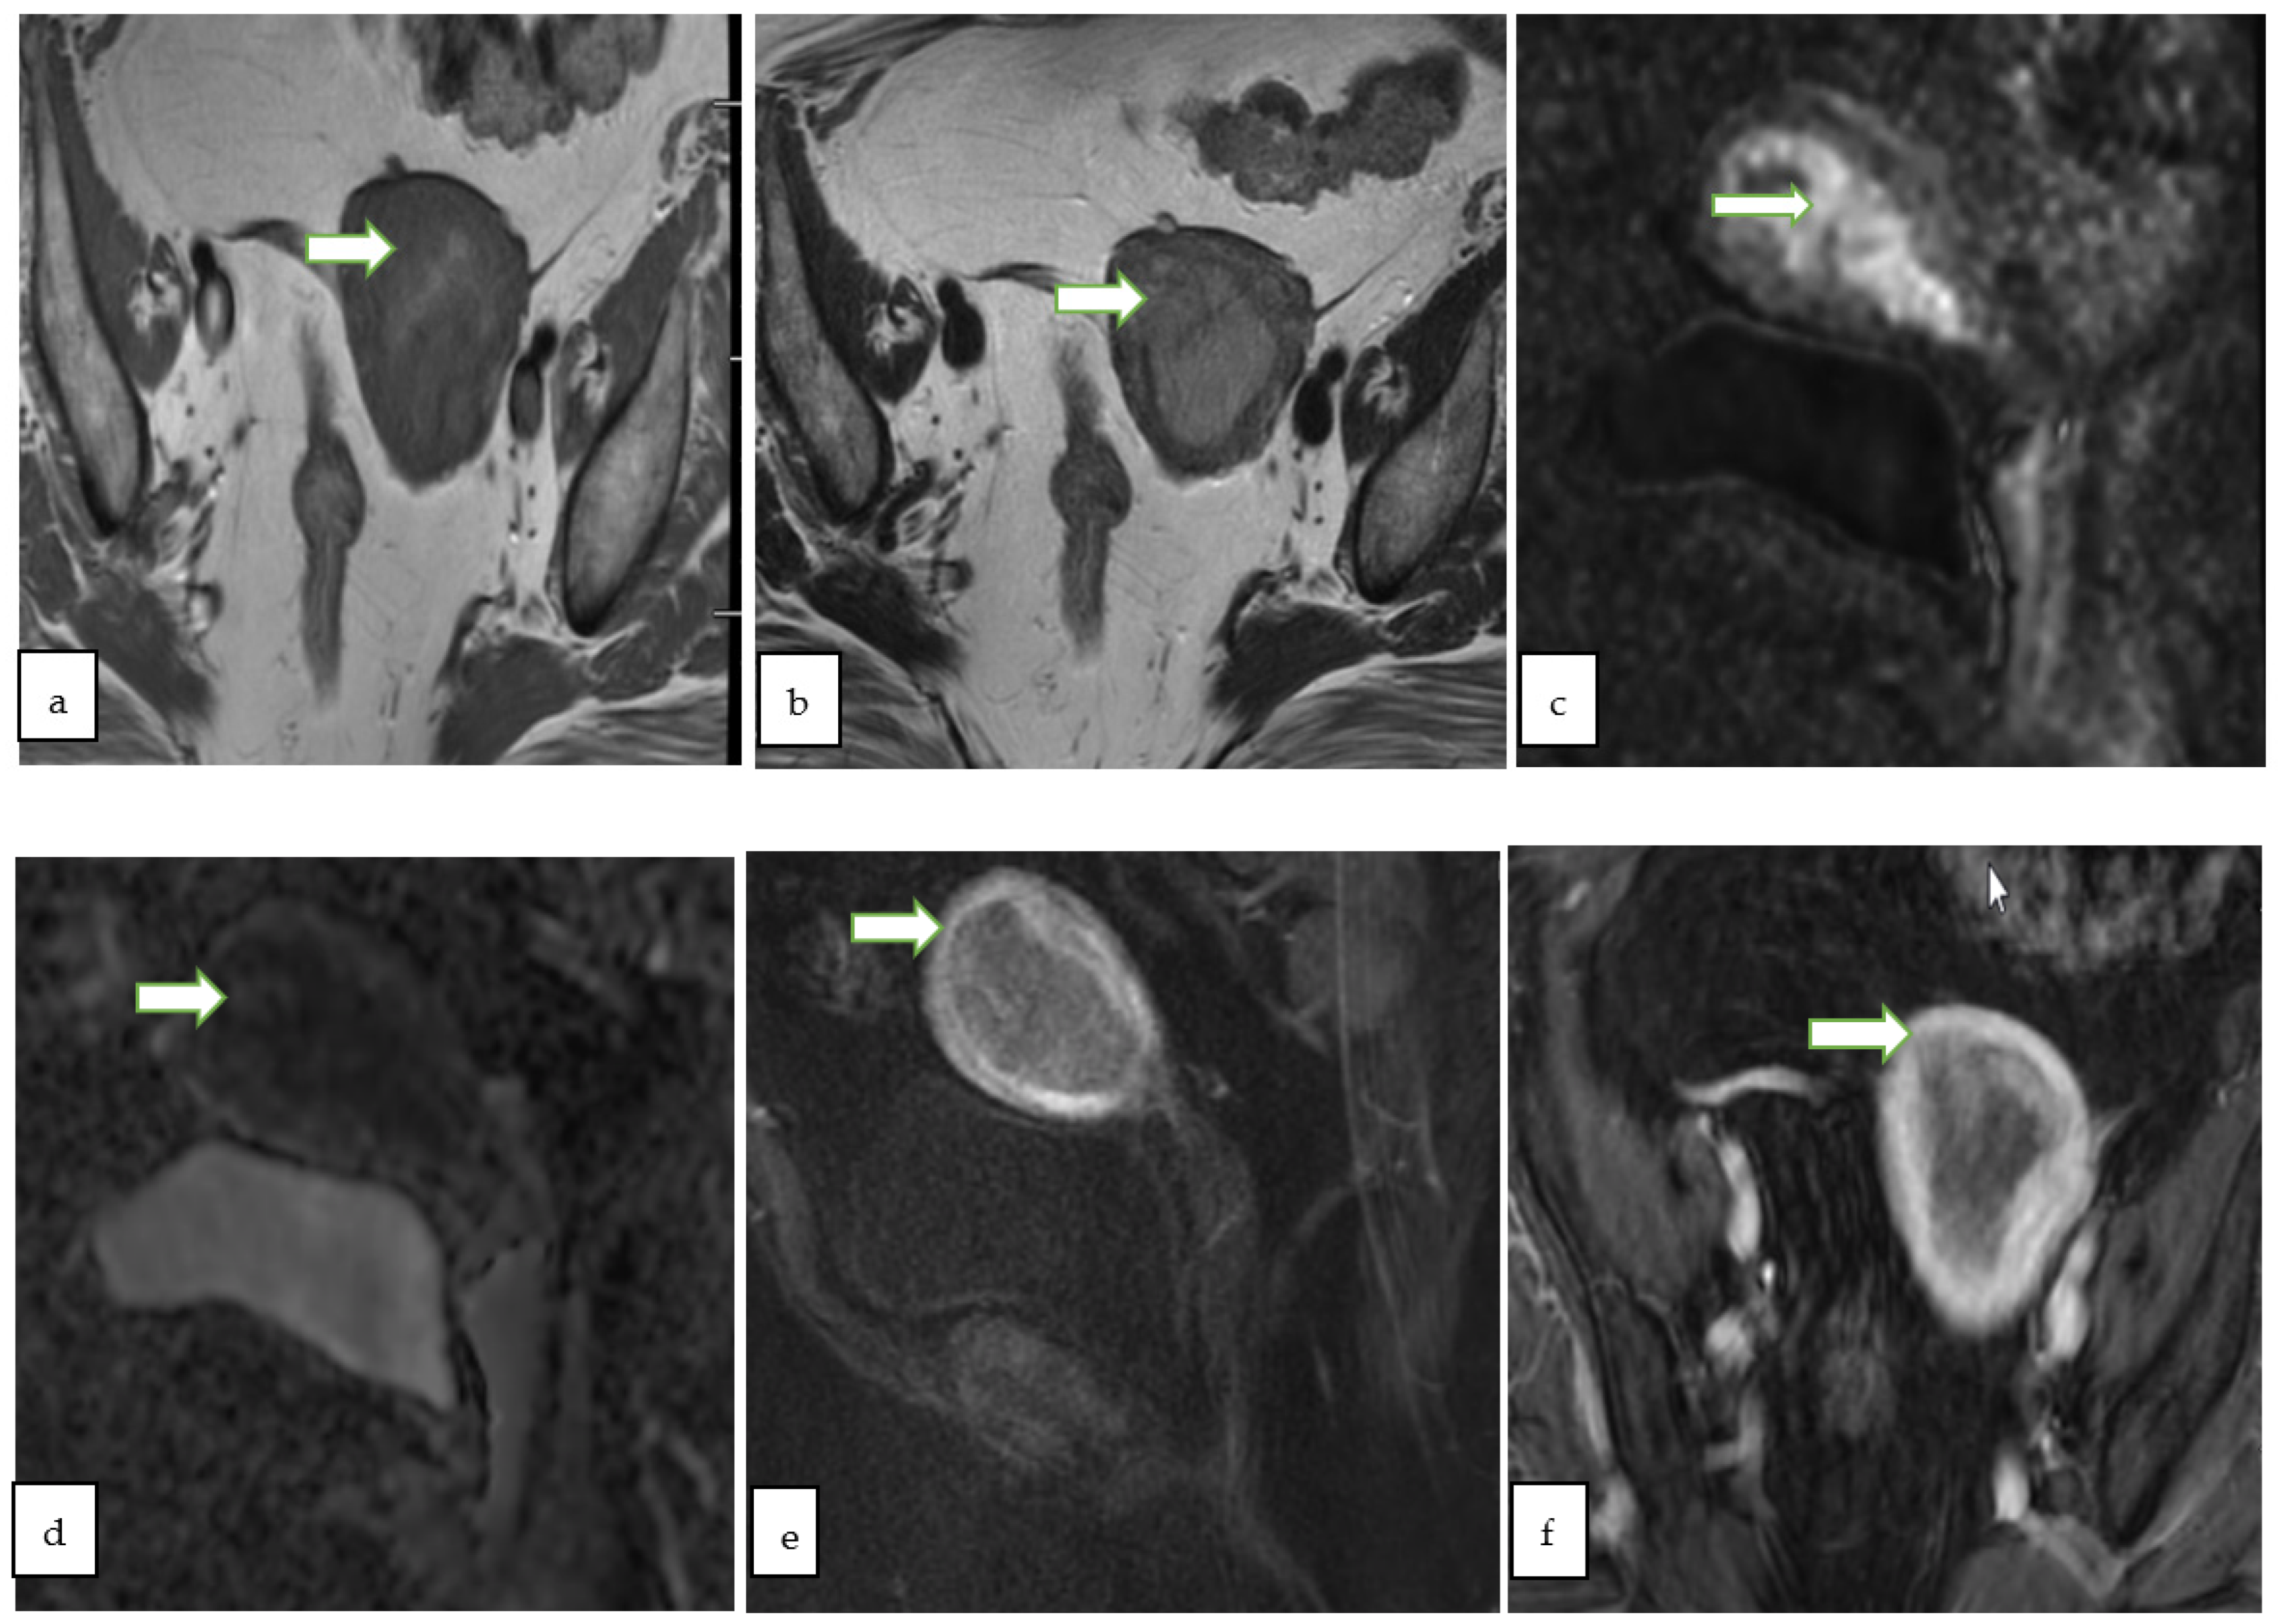

4.2. Magnetic Resonance Imaging (MRI)

- Thomassin-Naggara, I.; Poncelet, E.; Jalaguier-Coudray, A.; Guerra, A.; Fournier, L.S.; Stojanovic, S.; Millet, I.; Bharwani, N.; Juhan, V.; Cunha, T.M.; et al. Ovarian-Adnexal Reporting Data System Magnetic Resonance Imaging (O-RADS MRI) Score for Risk Stratification of Sonographically Indeterminate Adnexal Masses. JAMA Netw. Open 2020, 3, e1919896. [Google Scholar] [CrossRef]

- Sadowski, E.A.; Thomassin-Naggara, I.; Rockall, A.; Maturen, K.E.; Forstner, R.; Jha, P.; Nougaret, S.; Siegelman, E.S.; Reinhold, C. O-RADS MRI Risk Stratification System: Guide for Assessing Adnexal Lesions from the ACR O-RADS Committee. Radiology 2022, 303, 204371. [Google Scholar] [CrossRef]

| O-RADS MRI Score | Risk Category | Positive Predictive Value for Malignancy | Lexicon Description |

| 2 | Almost certainly benign | <0.5% | Cyst: Unilocular- any type of fluid content - No wall enhancement - No enhancing solid tissue * |

| 3 | Low risk | ~5% | Cyst: Unilocular–proteinaceous, hemorrhagic or mucinous fluid content - Smooth enhancing wall - No enhancing solid tissue |

| Cyst: Multilocular-Any type of fluid, no lipid content - Smooth septae and wall with enhancement-No enhancing solid tissue | |||

| Lesion with solid tissue (excluding T2 dark/DWI dark) - Low risk time intensity curve on DCE MRI | |||

| Dilated fallopian tube - Non-simple fluid: Thin wall/folds - Simple fluid: Thick, smooth wall/folds - No enhancing solid tissue | |||

| 4 | Intermediate risk | ~50% | Lesion with solid tissue (excluding T2 dark/DWI dark) - Intermediate risk time intensity curve on DCE MRI - If DCE MRI is not feasible, score 4 is any lesion with solid tissue (excluding T2 dark/DWI dark) that is enhancing ≤ myometrium at 30–40 s on non-DCE MRI |

| Lesion with lipid content - Large volume enhancing solid tissue | |||

| 5 | High risk | ~90% | Lesion with solid tissue (excluding T2 dark/DWI dark) - High risk time intensity curve on DCE MRI - If DCE MRI is not feasible, score 5 is any lesion with solid tissue (excluding T2 dark/DWI dark) that is enhancing > myometrium at 30–40 s on non-DCE MRI |

| Peritoneal, mesenteric or omental nodularity or irregular thickening with or without ascites |